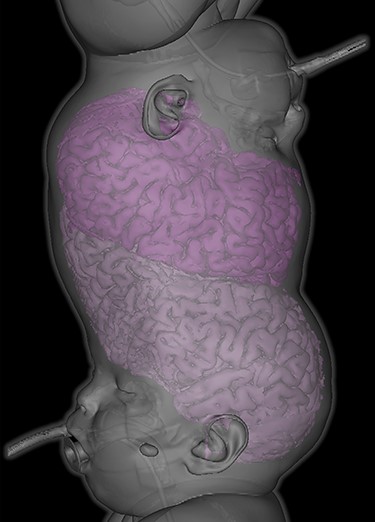

Tissue expansion performed to enable separation and craniofacial reconstruction.

In the first of four staged surgical separation procedures, we performed tissue expansion to permit separation and craniofacial reconstruction (Fig. 2). During this procedure, full anterior and posterior segment examination was achieved under general anesthesia. Examination findings for Twin 1 included right lagophthalmos of 3 mm (Fig. 3) due to abnormally high brow position causing right corneal punctate epithelial erosions, visualized using the Keeler Portable Slitlamp (Keeler Ltd, Windsor, UK). Anterior segment examination was otherwise normal. Indirect ophthalmoscopy revealed normal macular reflexes and healthy optic discs with cup-disc ratios of 0.3. Twin 2 had the same findings as Twin 1, except right brow was comparatively higher, causing 6 mm lagophthalmos (Fig. 3) and exposure keratopathy in the form of more widespread punctate epithelial erosions. Both were treated with chloramphenicol 1% eye ointment QDS and sodium hyaluronate 0.2% eye drops Q2H, to both eyes, resulting in clear corneas within 2 weeks.